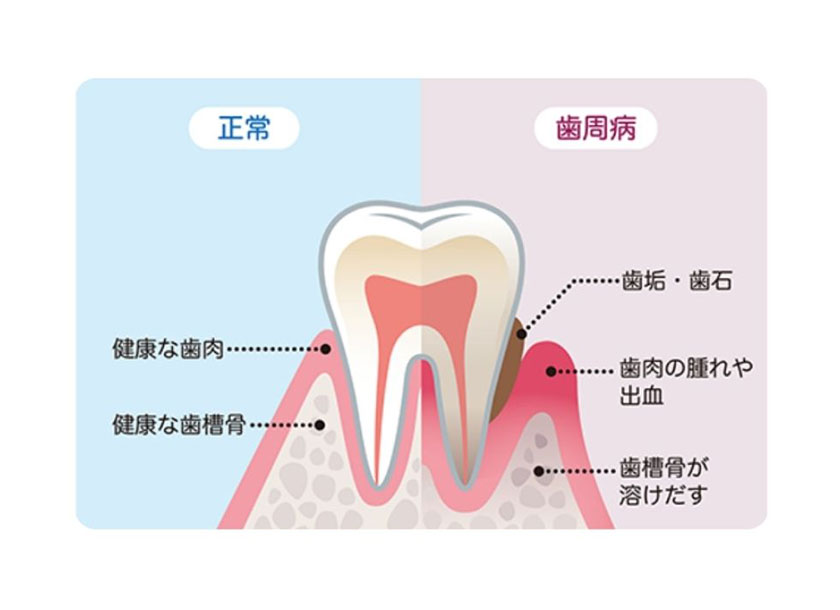

歯周治療について

歯は

『歯ぐき』

『セメント質』

『歯根膜(しこんまく)』

『歯槽骨(しそうこつ)』

の4つから構成される歯周組織に支えられています。

歯周病とはその原因菌によって、これらの歯周組織が少しずつ破壊されていく病気です。

虫歯とならび『歯科二大疾患』に挙げられる歯周病は歯の喪失原因のトップを占め、50代以降になると歯を失う原因の半数以上を占めるようになります。

成人の8割以上がかかるといわれる歯周病は、病状が進むまで症状があらわれにくく、発見が遅れやすいのが特徴です。